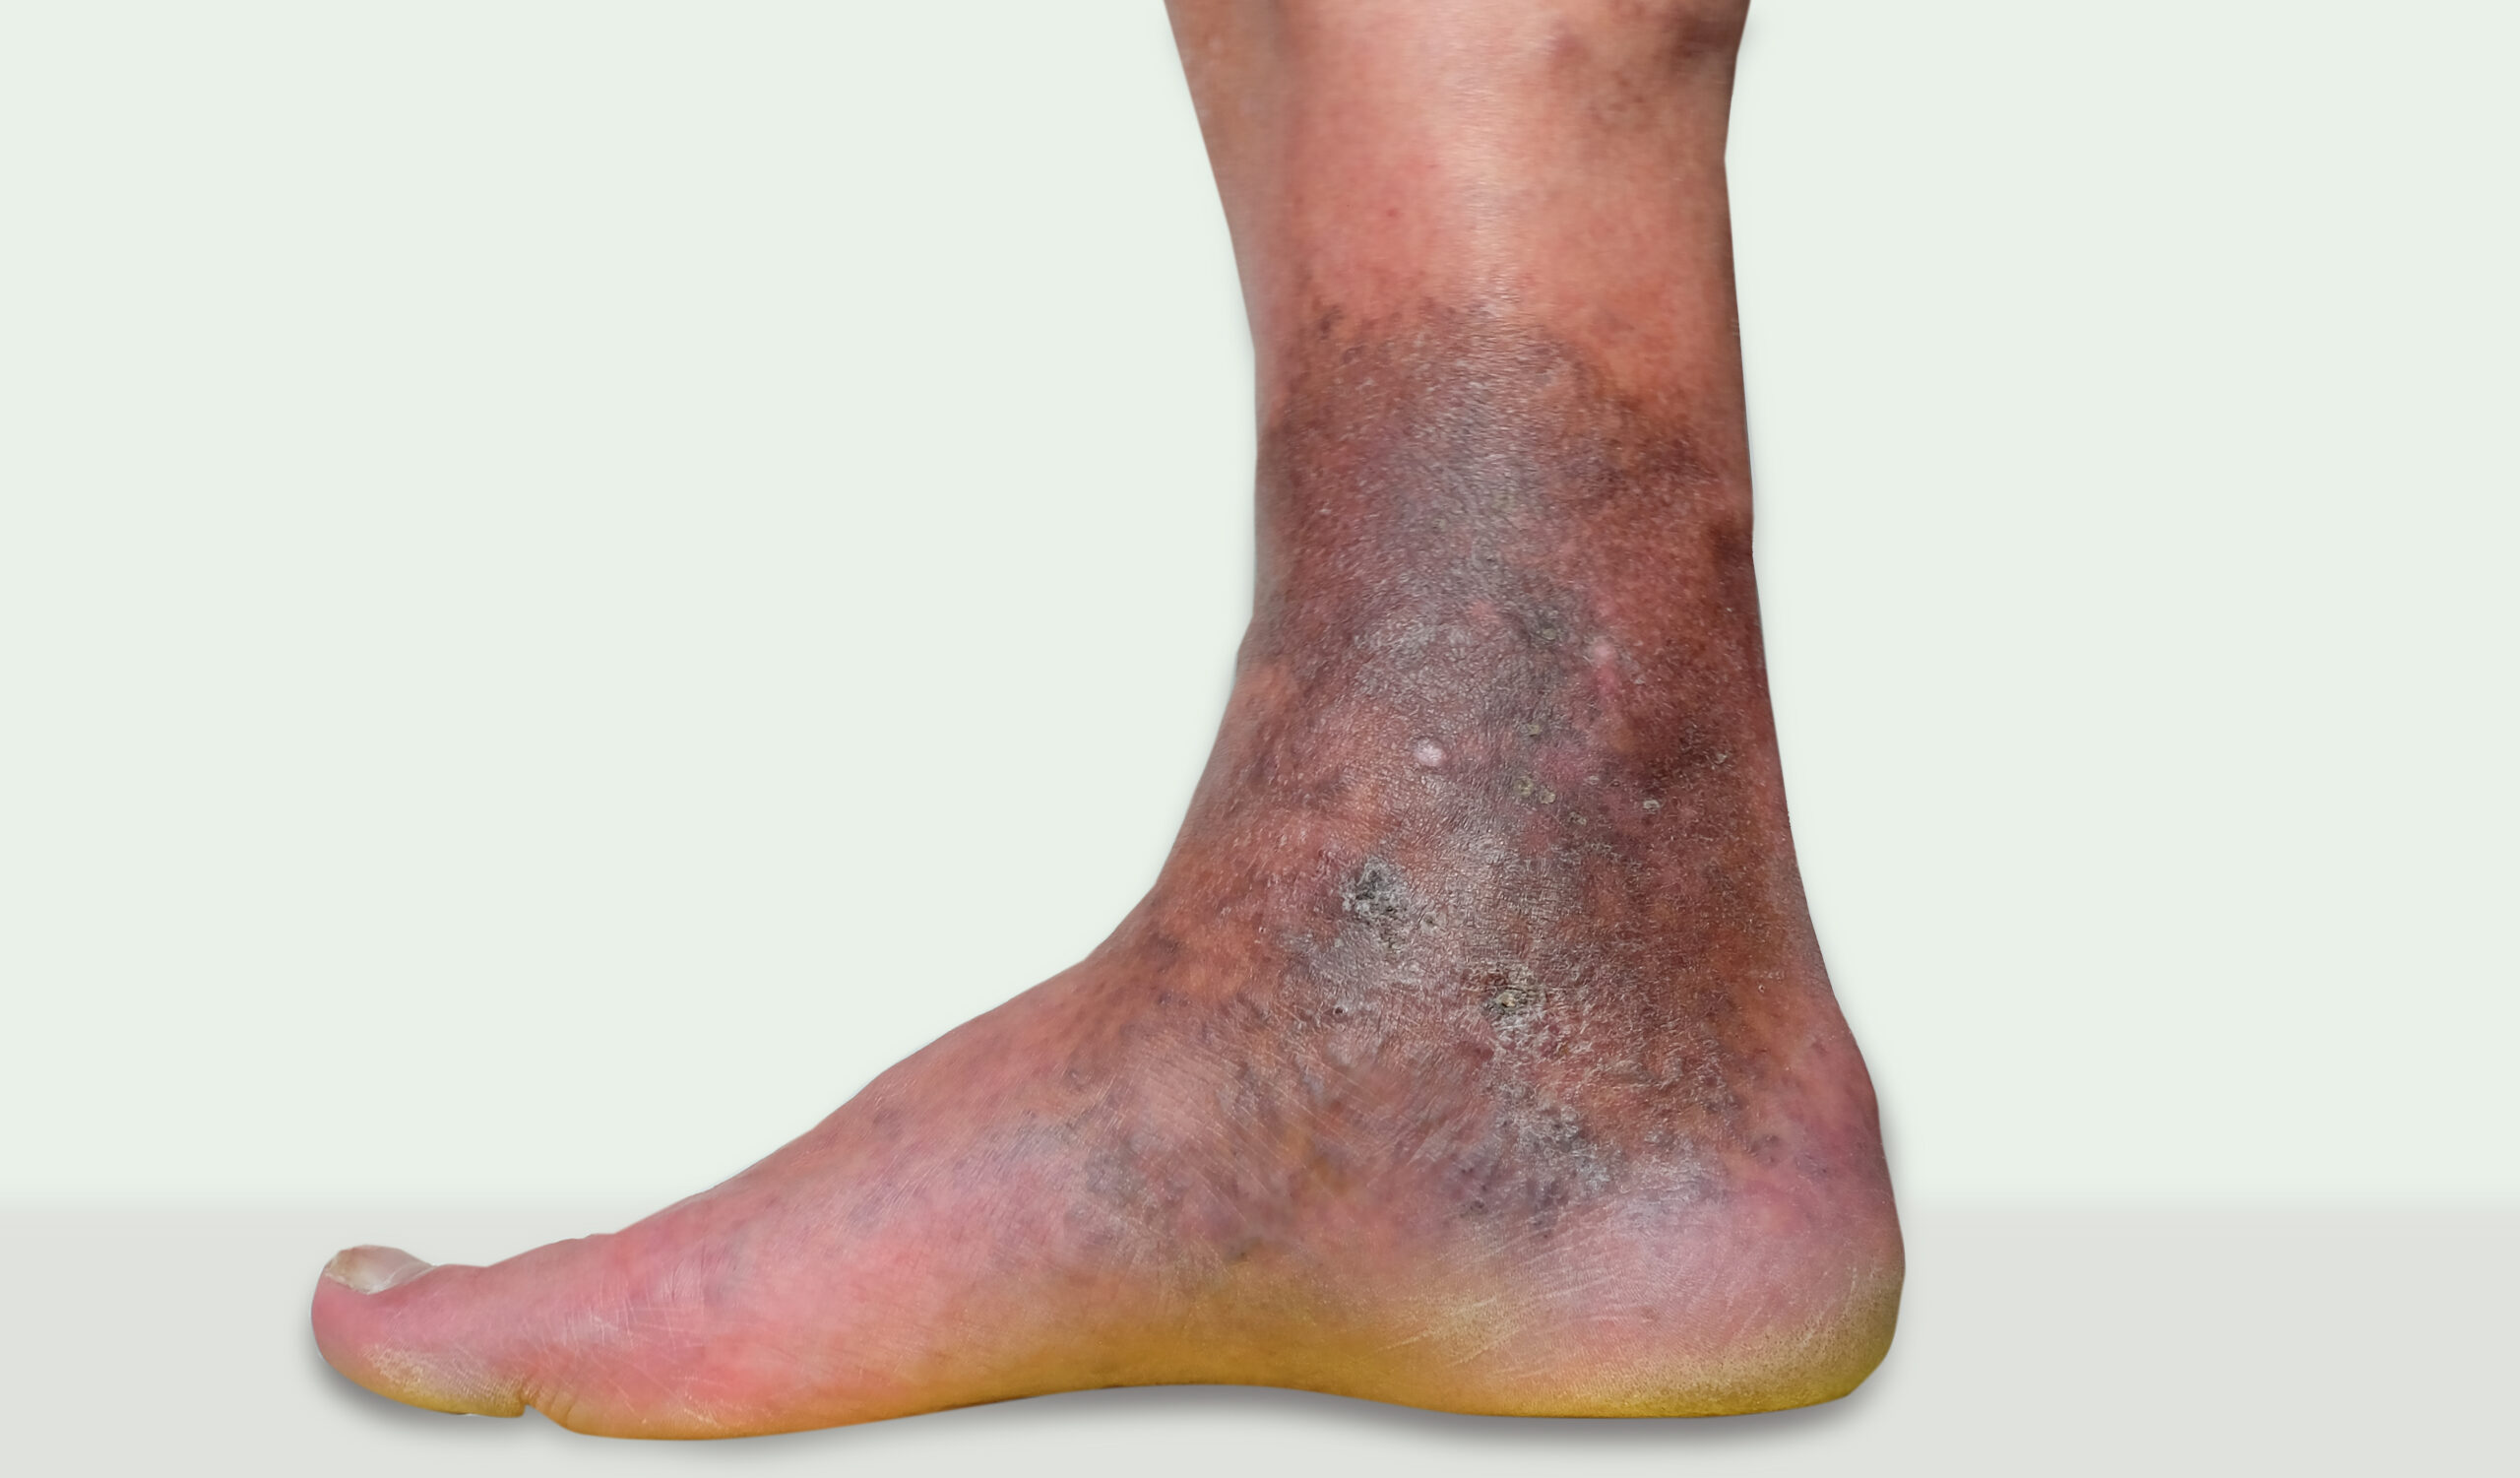

Changes in Skin Colour

Dark patches, redness, or pale skin may develop due to long-term circulation issues.

If you don’t pay attention to vascular problems, they can get worse over time and cause problems like severe pain, skin changes, ulcers that won’t heal, infections, or even gangrene. Seeing a vascular doctor in Jodhpur at the right time can help avoid these problems and make sure that treatment works better in the long run.

If varicose veins are left untreated, then they can start to progress from mild discomfort to more serious complications. And the complications can be:

• Constant swelling and feels heavy

• Changes in skin color, especially near the ankles

• In cases of more advanced disease, open wounds can occur

• Increase the risk of clotting and bleeding

So, if you notice any of the changes, then consult with a Vascular Surgeon near me for proper evaluation as well as timely treatment.